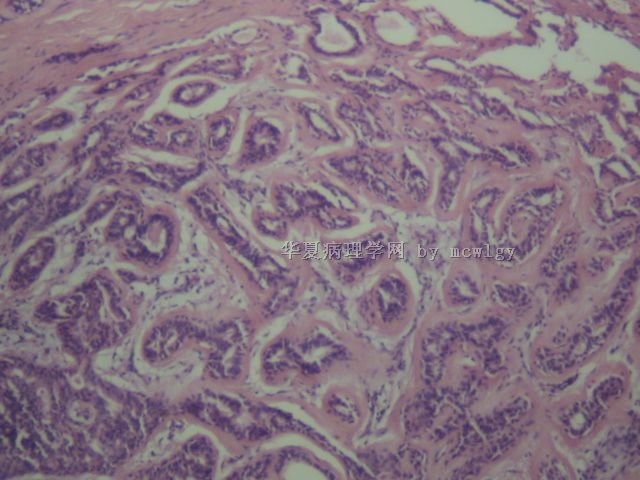

肉眼检查:  3*2*1CM结节界清,灰白。

标签:硬化性腺病 硬化性小叶增生

乳腺的,不是乳头乳晕的,肌上皮明显,有钙化,局灶导管上皮增生,乳头状。

良性。腺病之类,腺肌上皮瘤型?

Sclerosing adenosis

Focal papillary lesion (mostly benign) or papillary hyperplasia

microcalcification

Entire nodulle may be a fibroadenoma if it is a demarcated mass.

这例子缺乏完整的总体特征,主要由间质硬化和缺乏小叶结构的腺管组成,另外见导管增生性病变,根据这些图像推断,可能是纤维腺瘤样乳腺病(fibroadeinomatoid mastopathy),又称硬化性小叶增生(sclerosing lobular hyperplasia),这种病变多伴于纤维腺瘤或叶状肿瘤,而单独形成肿块很少见,本例有的图像也支持纤维腺瘤,而给出的图像硬化更明显。

从整个情况来看,1、病史应很长;2、从图13看,硬化性腺病的可能性更大,看不出包膜来